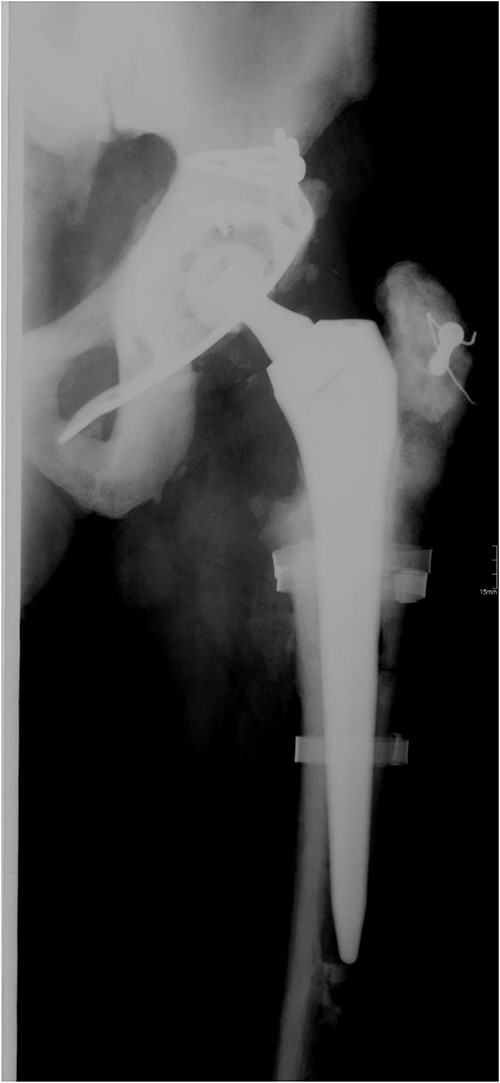

In 2011, a cementless THA of the right hip was done for the osteoarthritis. Three residual broken screws were present in the distal diaphysis from previous surgeries and were left in place (Fig. 3).

Anteroposterior radiograph of the right hip after THA with three broken residual screws in the distal diaphysis. (a) Anteroposterior hip radiograph with broken lateral plate. (b) Anteroposterior radiograph of the right hip after exchanging the femoral stem.

In 2013, the patient suffered a spontaneous Vancouver B2 periprosthetic fracture of the right THA. Osteosynthesis with a locking plate with screws and cerclages was done. Three months after the surgery, the plate broke and was exchanged with addition of an anterior plate and autologous spongioplasty. However, osteosynthesis failed 8 months later and the firmly ingrown femoral component was revised (Fig. 3a). Proximal femoral osteotomy resulted in several broken fragments. During removal of the broken screws, three sets of removal instruments were destroyed. A cementless revision modular stem was inserted and bone fragments fixed with cerclage wires and titanium tapes (Fig. 3b). Surgery took 6 h and he received six units of blood. Microbiological tissue samples were negative.